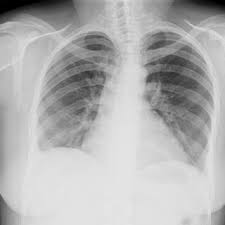

Chest X Ray Showing Mild Cardiomegaly With Normal Lung Fields During Download Scientific Diagram